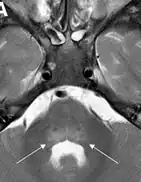

Common features included acute focal limb weakness and specific findings on magnetic resonance imaging (MRI) of the spinal cord consisting of nonenhancing lesions largely restricted to the grey matter. In most cases, these lesions spanned more than one level of the spinal cord. Some also had acute cranial nerve dysfunction with correlating nonenhancing brainstem lesions on MRI. None of the children experienced altered mental status or seizures. None had any cortical, subcortical, basal ganglial, or thalamic lesions on MRI. Most children reported a febrile respiratory illness in the two weeks preceding development of neurologic symptoms. In most cases, cerebrospinal fluid (CSF) analyses demonstrated mild-moderate pleocytosis (increased cell count in the CSF) consistent with an inflammatory or infectious process.

AFM is diagnosed by examining a person's nervous system in combination with reviewing images of the spinal cord. A doctor can examine a person's nervous system and the places on the body where he or she has weakness, poor muscle tone, and decreased reflexes. In addition, a doctor can do magnetic resonance imaging to look at a person's brain and spinal cord, do laboratory tests on the cerebrospinal fluid (CSF, the fluid around the brain and spinal cord), and may check nerve conduction (impulse sent along a nerve fiber) and response.[18]

Diagnosis of AFM requires acute onset limb paralysis and at least one gray-matter spinal-cord lesion. CSF should show pleocytosis.[19]

Children's Mercy Hospital, which had three or four cases in 2014, reported that the MRI images and symptoms closely mimicked polio. They reported: "The sudden onset of flaccid paralysis in single or multiple limbs with absolutely no sensory findings, the MRIs all showing uniformly a signal increase in the ventral horns of the spinal cord — this is exactly the same region of the spinal cord affected in polio ... Almost all of the patients have an increase in their white blood cells in the cerebrospinal fluid. Some of the patients have brainstem findings and cranial-nerve findings."[30]